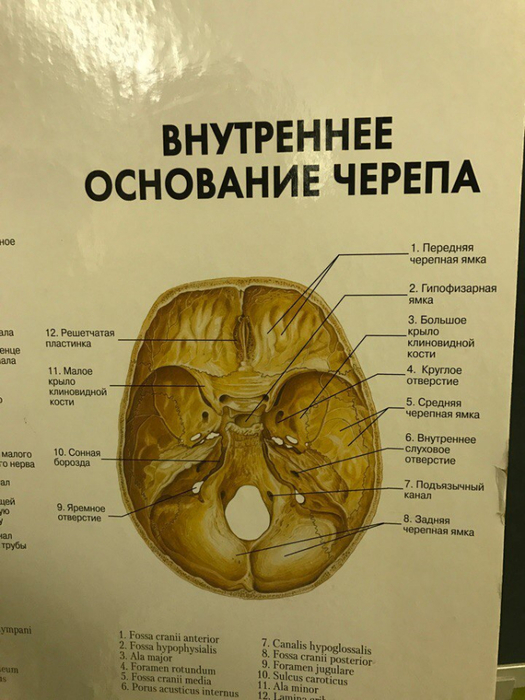

Анатомические детали: Фотографии топографии черепа с нижнего вида